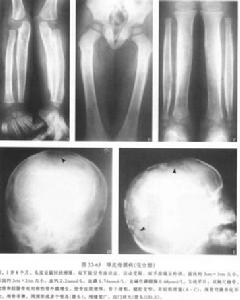

軟骨發育異常在乾骺端有大小不等形狀各異邊界清楚的軟骨化區呈柱狀排列X線上顯示成條紋狀乾骺端有不規則的擴大骨幹增厚及縮短變彎相鄰的骨骺呈斑點狀在指骨有膨大的不規則的囊性透亮區其中夾雜緻密的鈣化索條及斑點使指骨變形在髂骨可見軟骨柱呈扇形放射至髂嵴到了青年期看不到軟骨細胞柱而代之為密的斑點提示病變趨向癒合。